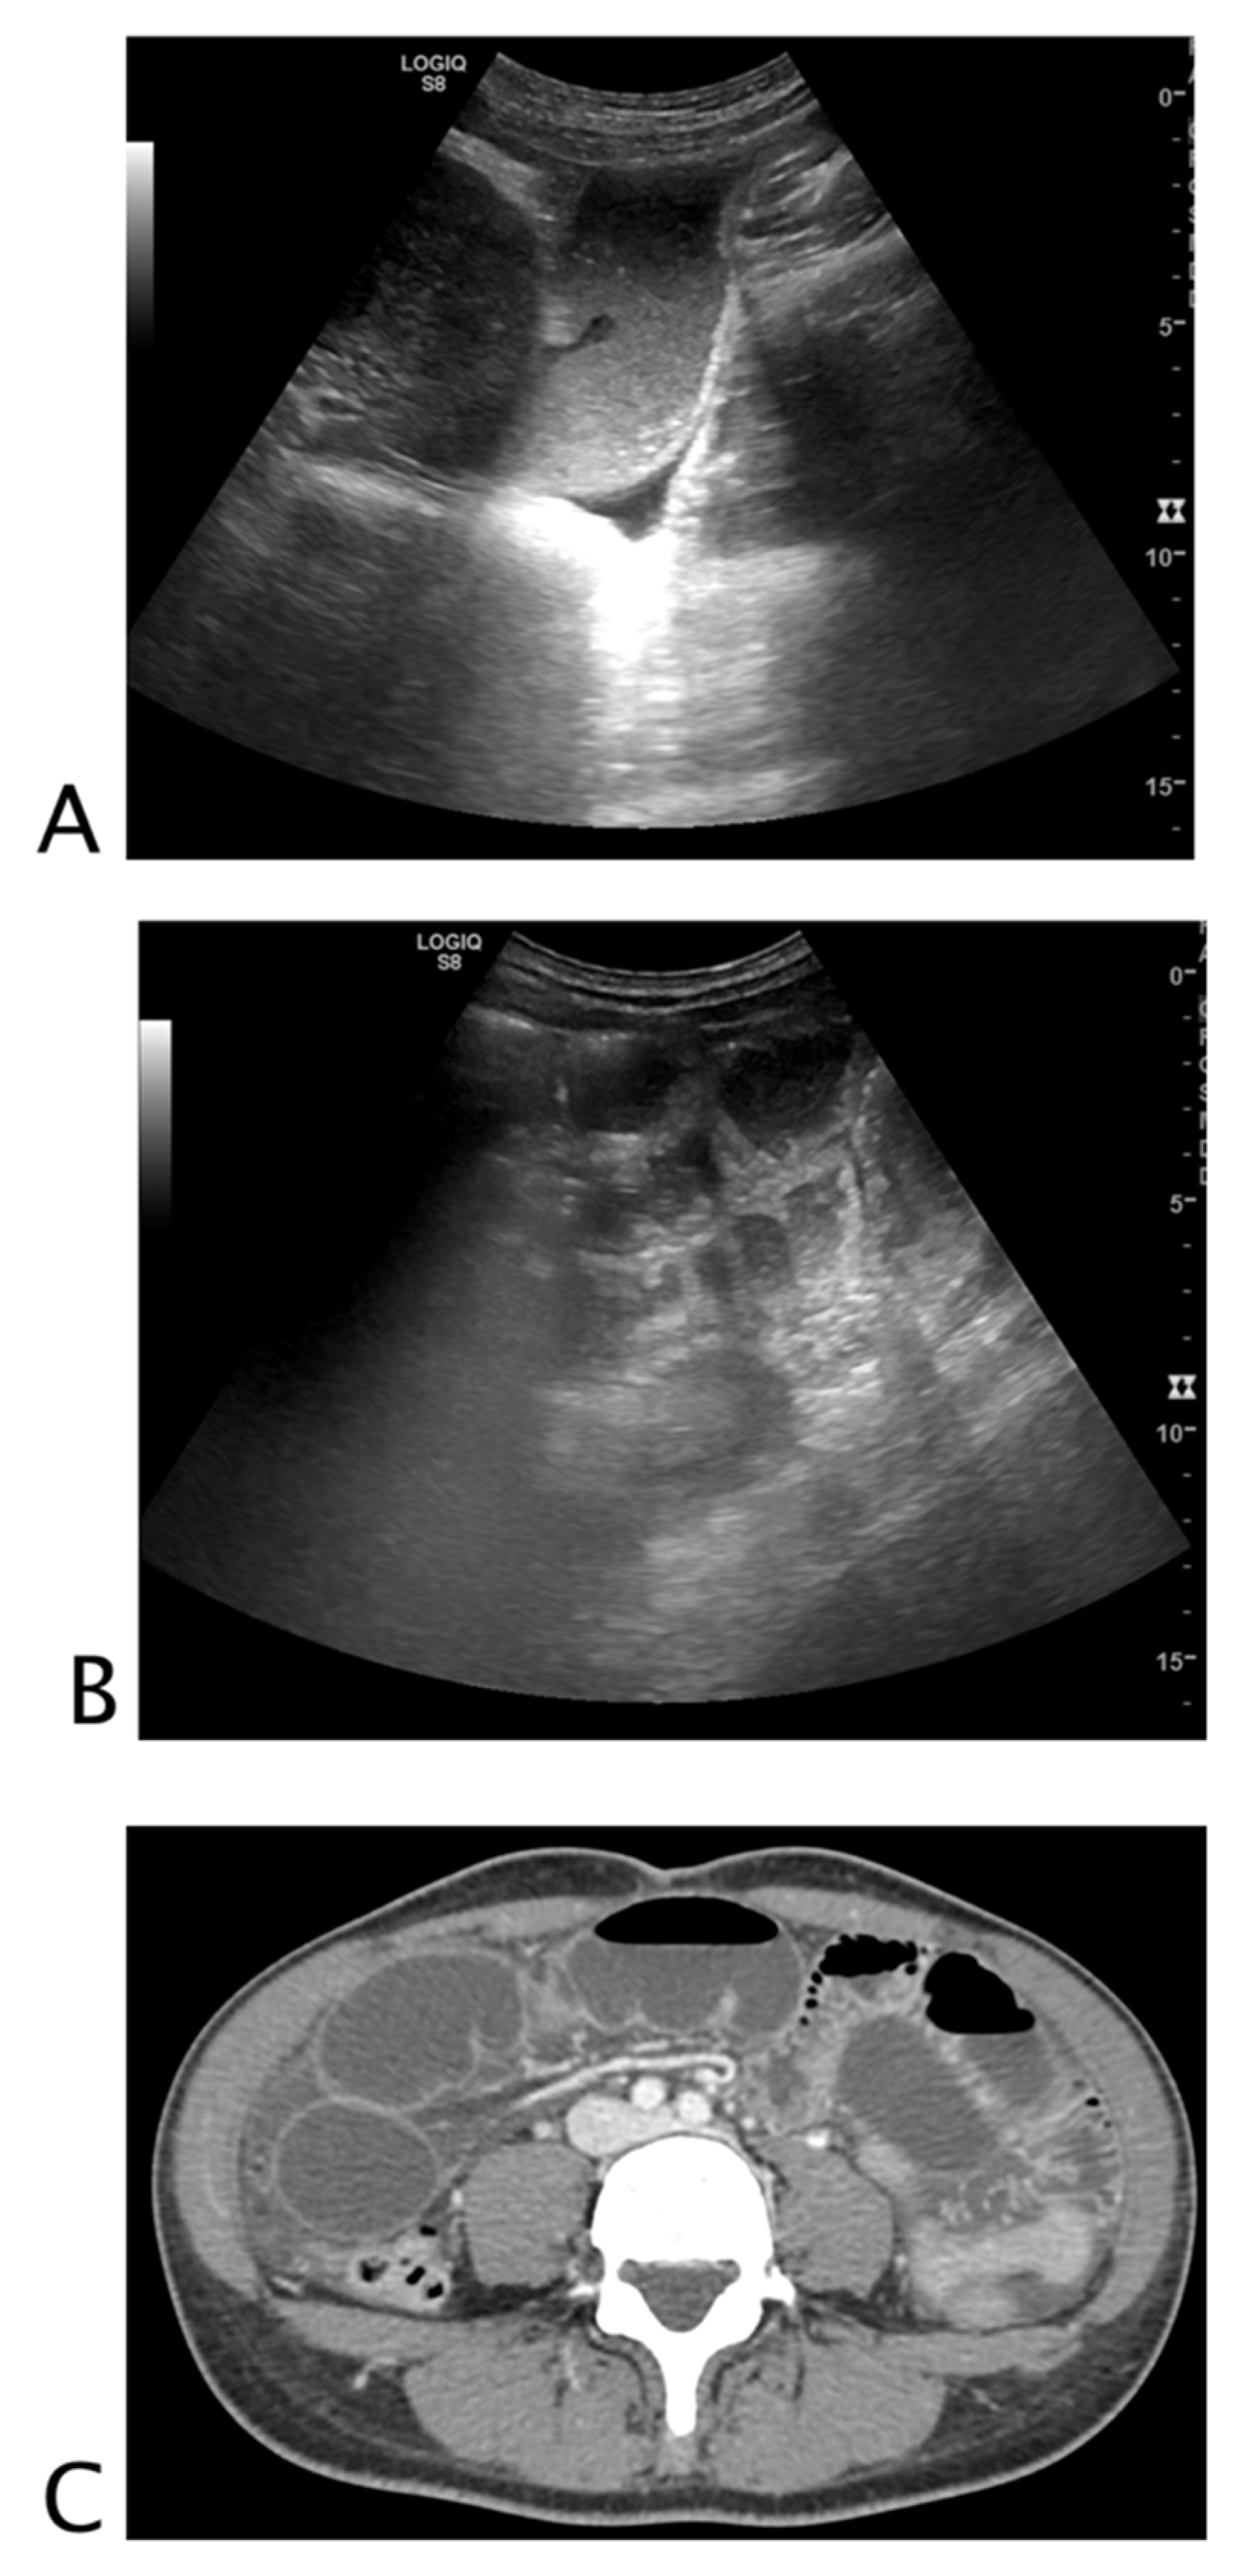

2.2.1. Vessels

2.3.1. Vessels

| Aorta | Aneurysm | Ruptured aneurysm | Thrombosis Dissection |